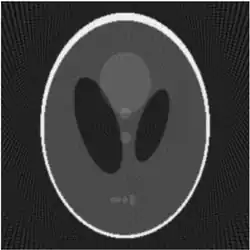

Concretely, for the two-dimensional Radon transform, the dual transform is given by: In the context of image processing, the dual transform is commonly called back-projection[4] as it takes a function defined on each line in the plane and 'smears' or projects it back over the line to produce an image.

In the two-dimensional case, the most commonly used analytical formula to recover from its Radon transform is the Filtered Back-projection Formula or Radon Inversion Formula[9]: where is such that .[9] The convolution kernel is referred to as Ramp filter in some literature.

Compared with the Filtered Back-projection method, iterative reconstruction costs large computation time, limiting its practical use. However, due to the ill-posedness of Radon Inversion, the Filtered Back-projection method may be infeasible in the presence of discontinuity or noise. Iterative reconstruction methods (e.g. iterative Sparse Asymptotic Minimum Variance[10]) could provide metal artefact reduction, noise and dose reduction for the reconstructed result that attract much research interest around the world.

Explicit and computationally efficient inversion formulas for the Radon transform and its dual are available. The Radon transform in dimensions can be inverted by the formula:[11] where , and the power of the Laplacian is defined as a pseudo-differential operator if necessary by the Fourier transform: For computational purposes, the power of the Laplacian is commuted with the dual transform to give:[12] where is the Hilbert transform with respect to the s variable. In two dimensions, the operator appears in image processing as a ramp filter.[13] One can prove directly from the Fourier slice theorem and change of variables for integration that for a compactly supported continuous function of two variables: Thus in an image processing context the original image can be recovered from the 'sinogram' data by applying a ramp filter (in the variable) and then back-projecting. As the filtering step can be performed efficiently (for example using digital signal processing techniques) and the back projection step is simply an accumulation of values in the pixels of the image, this results in a highly efficient, and hence widely used, algorithm.